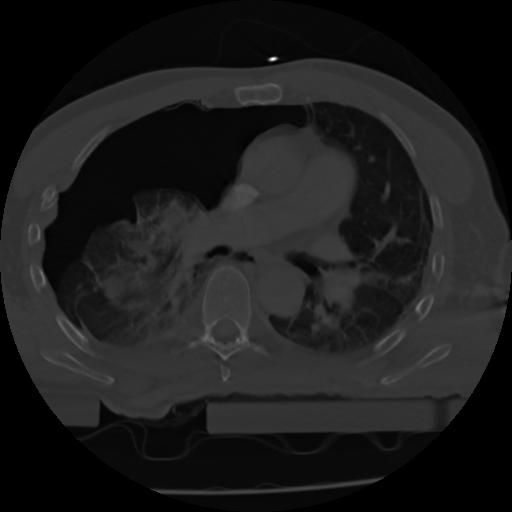

21 ANGIO,CE,Axial,3.0,ANGIO,,